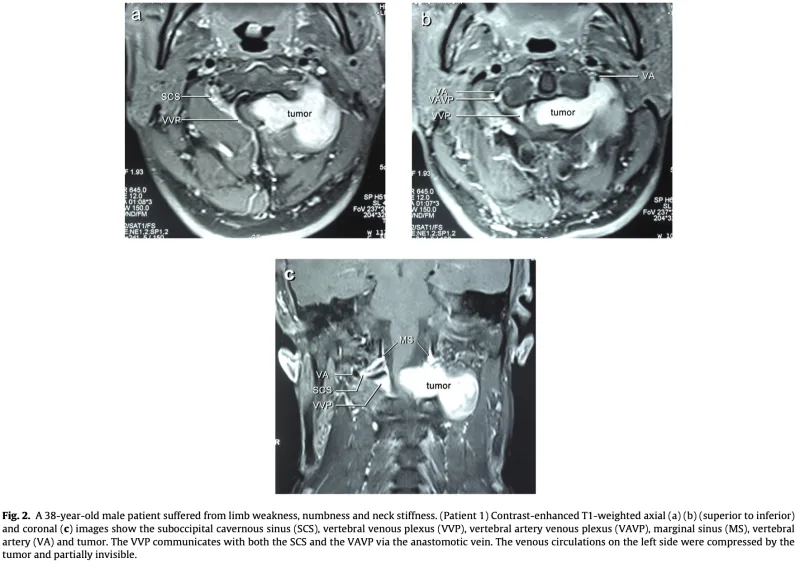

形成外科から, 頚部腫瘍を指摘された中高年の患者さんが紹介され, 受診されました.

「MRIで, 頚髄とつながっているように見える」

との情報でした。

MRIでは, 第1/2頚椎椎間孔から頚部後方へ隆起する腫瘍性病変を認め, 第2頚神経根から発生した神経鞘腫 と診断しました.

脊柱管内から神経根に沿って椎間孔を通り, 外側(傍脊柱)へと砂時計状に広がる腫瘍は, その形状からダンベル腫瘍と呼ばれます.

多くは良性の神経鞘腫です.

脊髄や神経根が圧排されると, 感覚障害, しびれ, 筋力低下などの麻痺症状を呈しますが, この患者さんは幸い, 現時点では症状は認められませんでした.

大学病院の整形外科および脳神経外科での精査・治療を勧め, 予約を取りました.